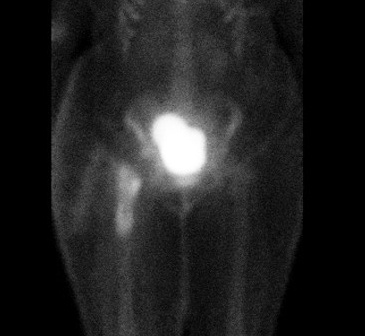

Infected THA on blood flow and blood pool

Infected THA on delayed phase